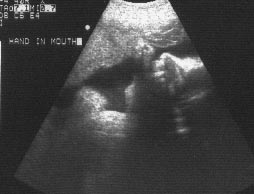

Ultrasound showing Benjamin's hand in his mouth